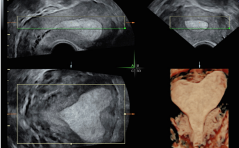

Sonoquiz

Woran denken Sie? PDF Dokument

Auflösung Sonoquiz

Tiefsitzender Sinus marginalis placentae PDF Dokument